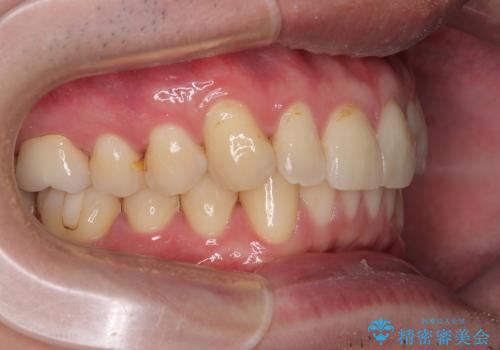

上下のデコボコを治したい インビザラインによる矯正治療

- 前歯のデコボコと突出感を気にして来院された患者様です。

極力目立たない装置を希望とのことで、インビザラインを用いて非抜歯で矯正治療を行うこととしました。

事前に親知らず4本を抜歯し、多少歯列を後方に移動できるように準備をした上で、なるべく歯と歯の間を削ることなくデコボコを解消できるように計画しました。

お仕事が忙しく、1日の装着時間は不十分となる日もありましたが、治療は順調に進めていくことができました。

途中、以前大きなむし歯で処置をした歯が痛み出し、根管治療が必要となったため、根管治療とオールセラミッククラウンによる補綴治療を行い、その後にインビザラインによる仕上げの歯列移動を行い、無事に治療を終えることができました。